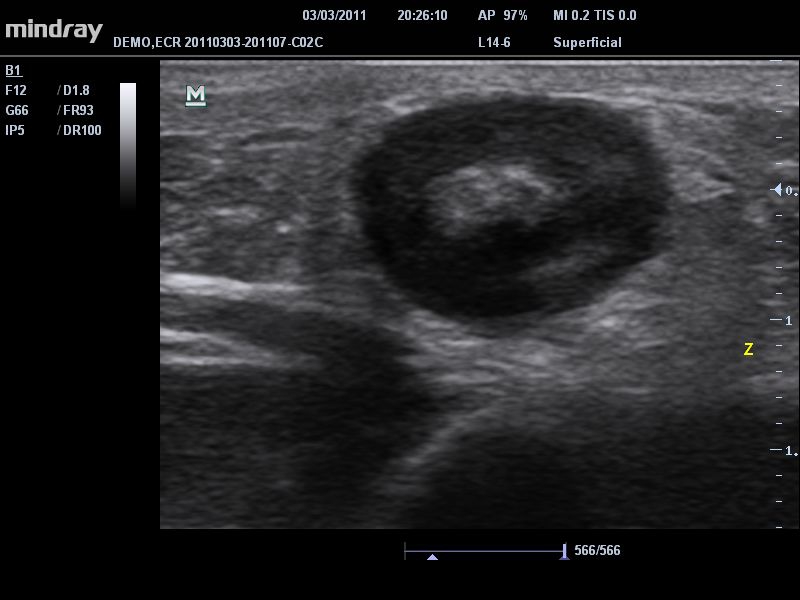

Mindray DC-T6

Ультразвуковая система Mindray DC-T6 – это инновационный аппарат для проведения высокого уровня диагностики с качественной визуализацией и широким спектром применения. Платформа рекомендована для использования в коммерчески многопрофильных медицинских учреждениях и государственных лечебных клиниках.

Возможности узи-сканера MIndray DC-T6

Система сочетает в удобном и компактном корпусе не только традиционные возможности современного УЗИ-сканера, но и инновационные технологии, повышающие точности диагностики состояния пациентов.